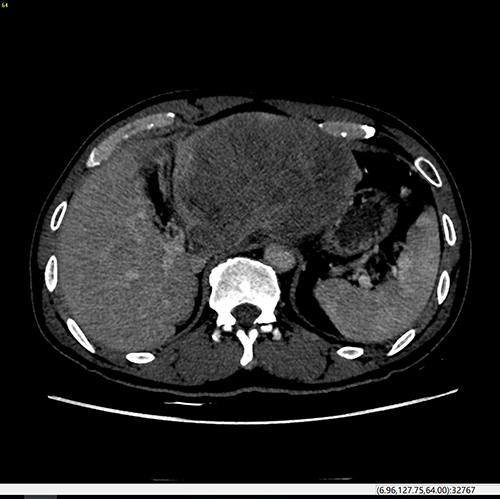

左肝癌--左半肝切除